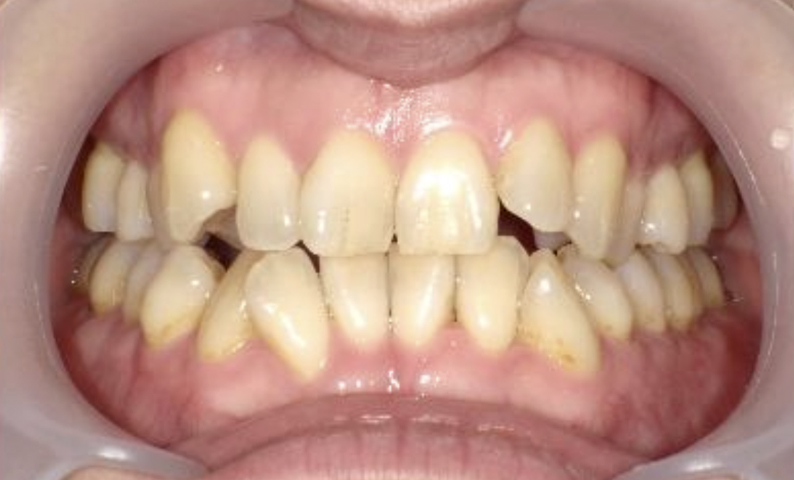

症例_003 上下顎の部分矯正

治療期間:12ヶ月金額:54万円+税男性八重歯前歯のガタガタ